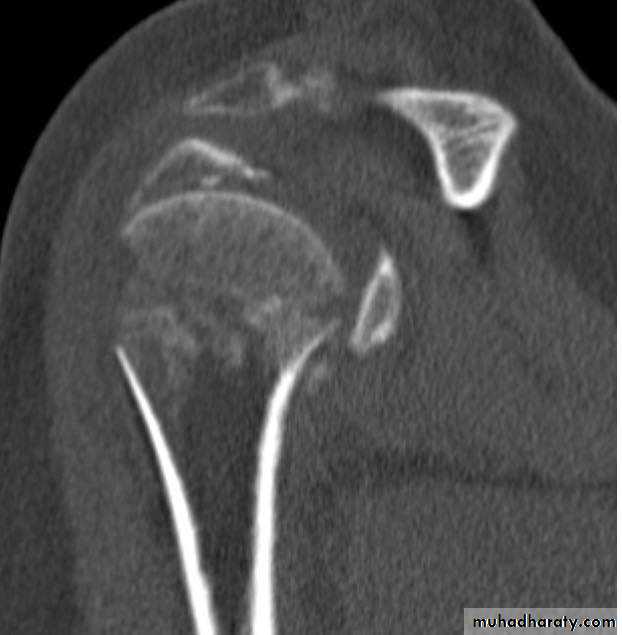

CT

29

34